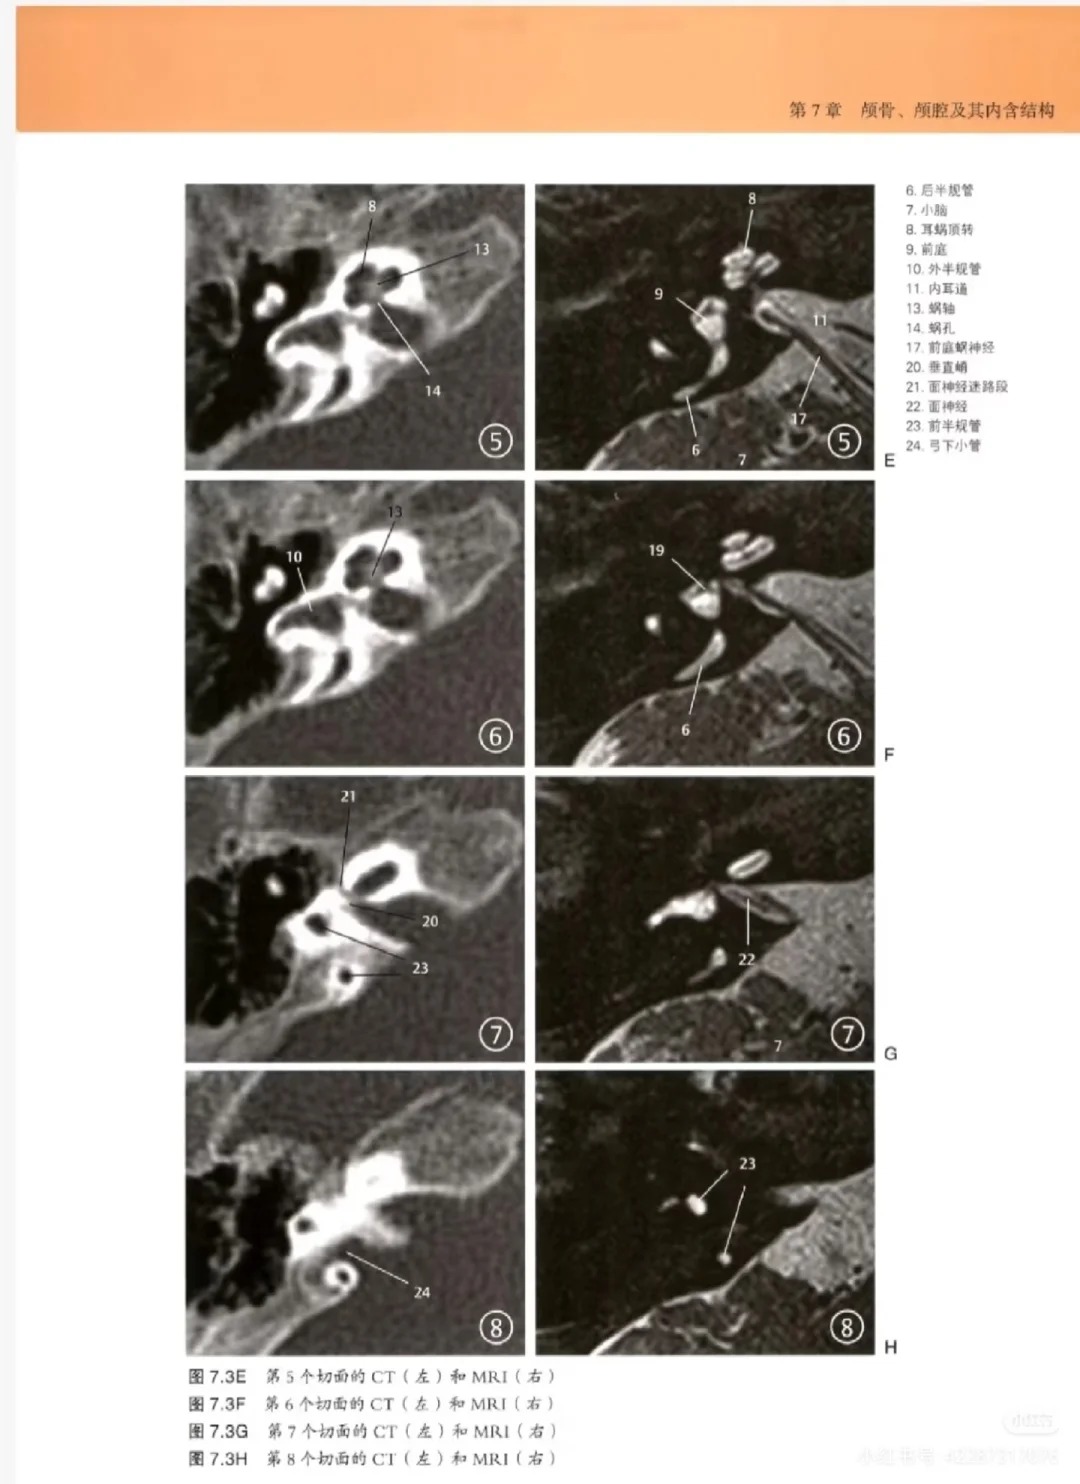

1. 双模态全覆盖,看片更高效:打破“MRI与CT分开查阅”的困境,一本书同时收录MRI和CT高清颅脑影像图,两种模态对比呈现,清晰展现不同模态下的影像特征,帮助使用者更全面、更深入理解病变特点,不用来回翻两本书,看片效率大幅提升。

2. 影像与解剖深度结合,破解看片难题:这是本书的核心王炸卖点,每一张颅脑影像图旁边,均配套高清解剖图+手绘示意图,精准对应解剖结构与影像表现,清晰标注关键部位,让使用者能快速将影像表现与解剖结构关联起来,彻底解决“对着片子找不着北、看不懂脑回路”的核心痛点,提升看片与诊断能力。

4. 高清大图,标注精准,直观易懂:全书采用高清大图呈现,影像图、解剖图清晰可辨,标注精准细致,关键解剖结构、病变部位一目了然,对于影像这种“看图说话”的学科,能大幅提升看片与学习效率,无论是临床看片还是日常学习,都能快速抓取核心信息。

• 双模态影像篇:全面收录颅脑MRI与CT高清影像图,对比呈现两种模态下的影像特征,涵盖正常影像与病变影像,助力全面理解病变表现。

• 影像+解剖对照篇:每一张影像图配套高清解剖图+手绘示意图,精准对应解剖结构,标注关键部位,帮助使用者快速关联影像与解剖,看懂颅脑结构。